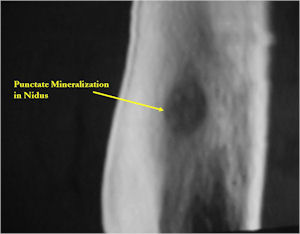

Plain X-Rays:

- Lucent nidus surrounded by a zone of marked sclerosis

- The nidus may demonstrate mineralization/ossification usually from the center outward that appears as a central zone of density within the nidus

- A nidus that is heavily ossified may blend in with the surrounding sclerosis and be difficult to detect on a plain x-ray.